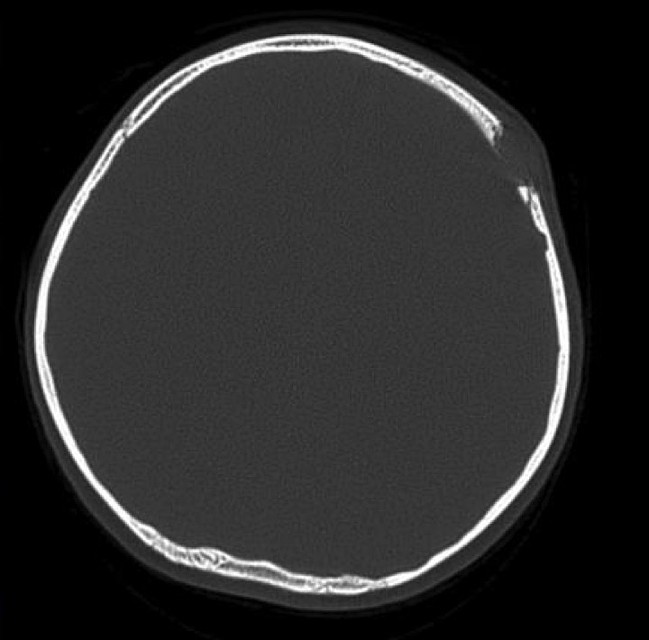

Так выглядит гранулема на изображении из томографа.

Та же гранулема, но в разрезе. Натуральная дырка.